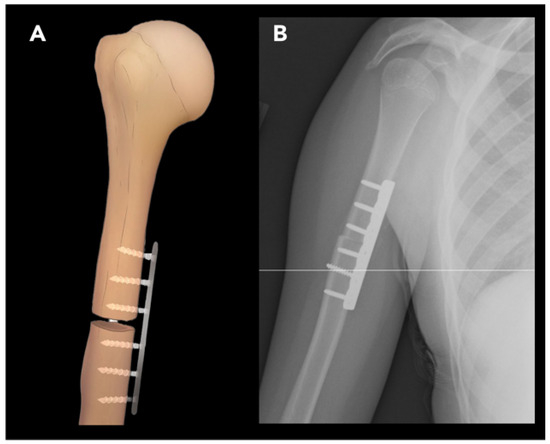

2.2.1. External Rotation Humeral Osteotomy

- Rühmann, O.; Lipka, W.; Bohnsack, M. External rotation osteotomy of the humerus for treatment of external rotation deficit in palsies. Oper. Orthopädie und Traumatol. 2008, 20, 145–156. [Google Scholar] [CrossRef] [PubMed]

- Acan, A.E.; Gursan, O.; Demirkiran, N.D.; Havitcioglu, H. Late treatment of obstetrical brachial plexus palsy by humeral rotational osteotomy and lengthening with an intramedullary elongation nail. Acta Orthop. Traumatol. Turc. 2018, 52, 75–80. [Google Scholar] [CrossRef]

- Akinci, M.; Ay, S.; Kamiloglu, S.; Ercetin, O. External rotation osteotomy of the humerus for the treatment of shoulder problems secondary to obstetric brachial plexus palsy. Acta Orthop. Traumatol. Turc. 2005, 39, 328–333. [Google Scholar]

- Bae, D.S.; Waters, P.M. External rotation humeral osteotomy for brachial plexus birth palsy. Tech. Hand Up. Extrem. Surg. 2007, 11, 8–14. [Google Scholar] [CrossRef]

- Abdelgawad, A.A.; Pirela-Cruz, M.A. Humeral rotational osteotomy for shoulder deformity in obstetric brachial plexus palsy: Which direction should I rotate? Open Orthop. J. 2014, 8, 130. [Google Scholar] [CrossRef]